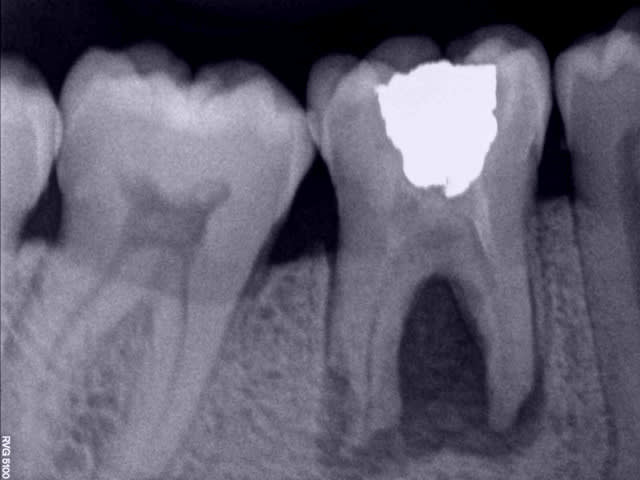

sniff périimplantite

J'ai quelques d'implants avec la même image et je ne touche à rien si l'implant est immobile. Et certains sont là depuis des années...

Une perte osseuse non infectée n'est pas une périimplantite et elle se stabilise à un certain niveau lorsque le système est en bio-équilibre.

Ici, il est dommage que l'implant soit un peu court, ce qui peut entrainer sa perte par surcharge.

Je ne pense pas que ce soit une périimplantite et le tabac n’est pas la cause de la perte osseuse mais un facteur aggravant.